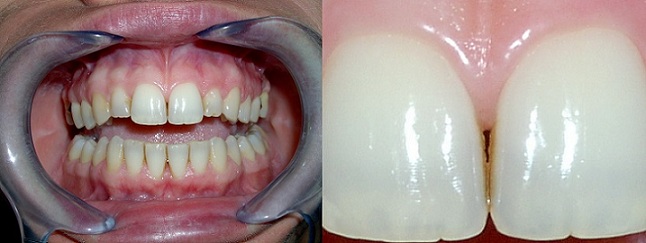

SBIANCAMENTO DENTALE

Il cambiamento di colore di un dente è un segnale importante da non trascurare mai.

Tale evento è quasi sempre associato alla perdita di vitalità dell'elemento ed è sempre la spia di un processo che sta avvenento interamente al dente.

Le cause sono spesso legate ad un trauma avvenuto anche parecchi anni prima, oppure, a pregresse carie, anche già, che hanno innescato il processo involutivo del tessuto pulpare contenuto nel dente. Talvolta è difficle risalire all'evento scatenante proprio per la lunga latenza di tempo che intercorre tra i due eventi.

La perdita di vitalità di un elemento dentale è causata dalla morte del nervo in esso contenuto e, oltre a produrre una decolorazione antiestetica sulla corona visibile, può causare un'infezione nell'osso in corrispondenza della parte terminale della radice. Talvolta questa lesione può diventare cronica e rimanere silente per molti anni ma in altri casi può acutizzarsi provocare un dolorosissimo ascesso.

In altri casi, anche se decisamente più rari, queste lesioni possono trasformarsi in grosse cisti che possono coinvolgere numerosi denti adiacenti e che richiedono veri e propri interventi chirurgici per la loro rimozione.

Una visita di controllo ed una semplice radiografia ci permetteranno di fare una diagnosi completa e di proporre un trattamento adeguato per curare il dente e riportarlo al suo colore naturale.

Tale trattamento è assolutamento indolore e consiste nell'applicazione di sostanze sbiancanti nella parte interna del dente.

Il risultato ottenuto è strettamente dipendente dalla meticolosità con cui la tecnica viene applicata e non è assolutamente invasiva per il paziente. I risultati sono già visibili entro pochi giorni dall'inizio del trattamento.